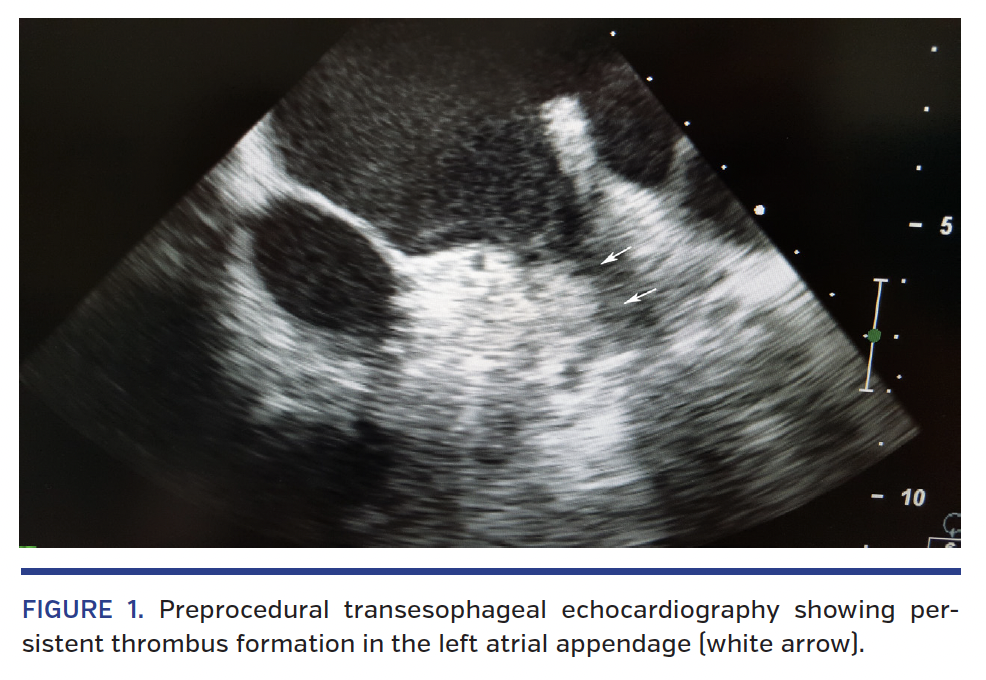

A 78-year-old male who was on warfarin presented with history of arterial hypertension, diabetes mellitus, remote spontaneous hemorrhagic pericardial effusion, permanent AF, and a previous hemorrhagic gastritis. He was transferred after a recent subdural hematoma under dabigatran to perform transesophageal echocardiography for the purpose of evaluating the feasibility of transcatheter LAA closure. Unfortunately, echocardiogram showed the presence of thrombus formation in the LAA. Anticoagulation with low-molecular-weight heparin and aspirin was resumed, but thrombus persisted in LAA at 1 month with ultrasound follow-up (Figure 1). After multidisciplinary discussion with a cardiac surgeon, neurologist, and interventionalist, we performed transcatheter LAA closure with TriGuard HDH embolic cerebral protection device (Keystone Heart, Ltd) (Figure 2). Then, the cerebral protection system was removed and angiographic control of the renal and mesenteric arteries was performed to exclude distal embolization. We didn’t perform angiography of the supraaortic trunks because of the lack of any neurological dysfunction. LAA closure is a valuable alternative in patients with absolute contraindication to long-term anticoagulation due to high bleeding risk. Although the presence of thrombus in the LAA is a prohibitive condition to the invasive procedure, the cerebral distal protection device allowed to safely conduct transcatheter LAA closure, reducing the risk of cerebral embolization linked to periprocedural thrombus mobilization or manipulation. The patient was discharged with dual-antiplatelet therapy (aspirin 100 mg and clopidogrel 75 mg daily) for 1 month.